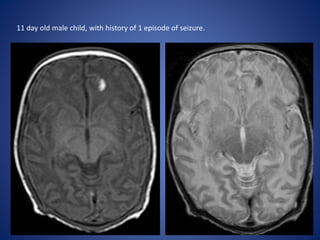

11 day old male child, with history of 1 episode of seizure.

11 day oldmale child, with history of 1 episode of seizure.